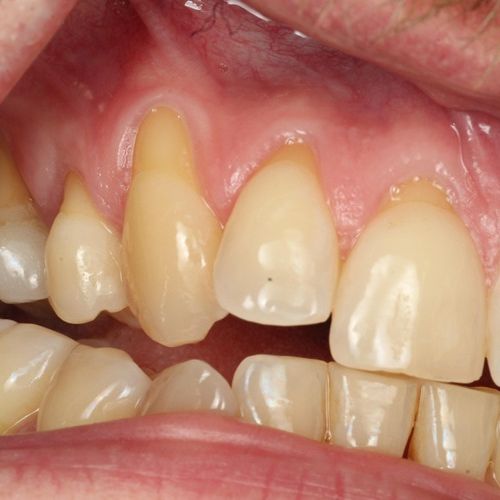

![]() | ![]() |

| Untreated severe gum disease | Gum disease treated and stabilised by Dr Halai |